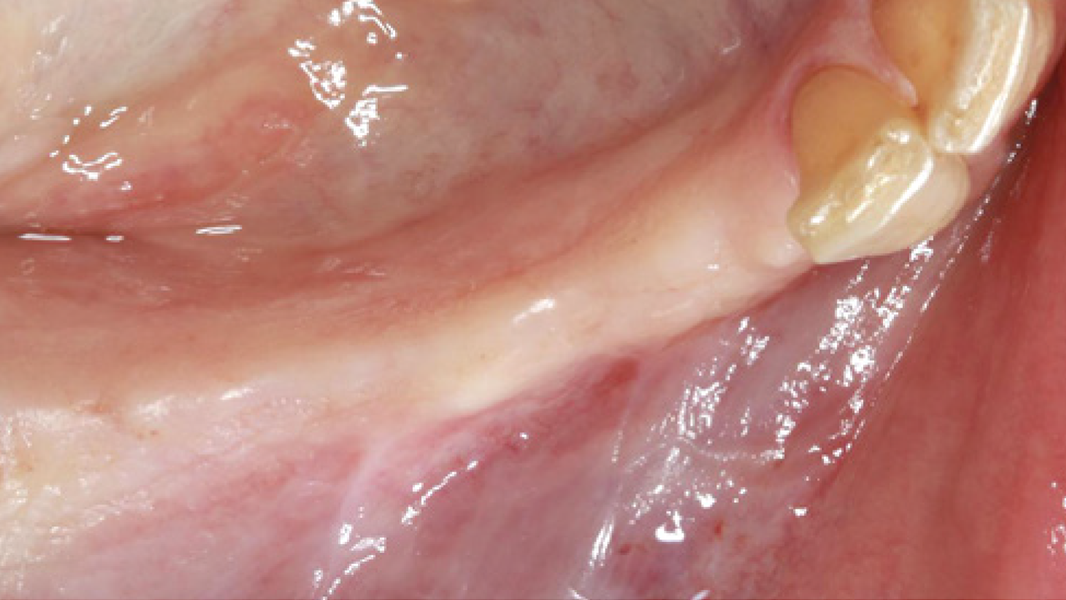

Klinische Erfahrungen MinerOss A + HYA

- 85 % der Kliniker bewerteten die Anwendung des „Sticky Bone“ als „einfacher“ oder „viel einfacher“ verglichen mit herkömmlichen Partikeln.14, 17

- Die Präparation des „Sticky Bone“ wurde weitgehend als einfach beschrieben und von den Klinikern mit 8,9 auf einer Skala von 1 (am schwierigsten) bis 10 (am einfachsten) bewertet.14

- Auf einer Skala von 1 bis 10 bewerteten die Kliniker die Heilung des Weichgewebes innerhalb der ersten zwei Wochen mit 8,8 bei den Erstanwendern.14, 17